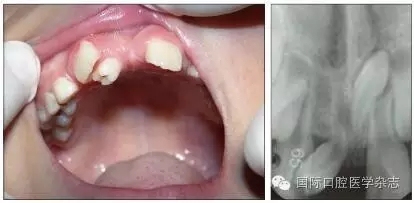

牙外傷引起的牙髓壞死、根尖周病變可能導(dǎo)致繼承恒牙發(fā)育或萌出方向的改變,因此,所有的乳牙外傷都應(yīng)定期復(fù)查,嚴(yán)密觀察牙髓狀態(tài)及根尖周病變的發(fā)生。如果乳牙嚴(yán)重挫入,特別是乳牙冠向唇側(cè)移位,根向腭側(cè)移位時(shí),X線片檢查發(fā)現(xiàn)乳牙牙根與恒牙胚大量重疊,應(yīng)及時(shí)拔除乳牙。由于恒牙胚多在乳牙根的腭側(cè),此時(shí)挫入的乳牙根可能會(huì)損傷壓迫恒牙胚,甚至牙胚移位,嚴(yán)重時(shí)即使拔除乳牙,也可能發(fā)生繼承恒牙釉質(zhì)發(fā)育不全,甚至埋伏阻生、牙齒畸形。圖4顯示為一8歲男孩,因上中切牙未萌前來就診,追問病史為3歲左右乳牙外傷,但未行任何處理,后因外傷乳牙變色,牙齦流膿而在診所行拔除術(shù),影像學(xué)檢查見右上中切牙為彎曲牙影像,牙冠與牙根不在同一軸線上[4]。

圖4 右上中切牙阻生(左),X線片顯示為彎曲牙(右)

Fig 4 Impaction of rightupper central incisor(left), X ray film showed the laceration tooth(right)